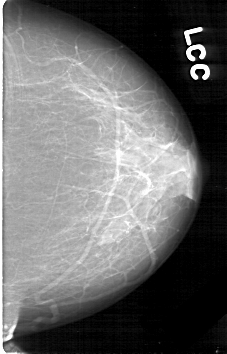

D_4149_1.LEFT_CC

LEFT_CC LINES 5296 PIXELS_PER_LINE 3391 BITS_PER_PIXEL 12 RESOLUTION 43.5 NON_OVERLAY